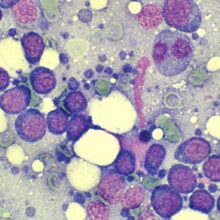

血管肉腫とは、血管内皮細胞という血管を構成する細胞が原因となる悪性腫瘍のことです。

非常に悪性度が高く、高い確率で全身へ転移すると言われています。

血管肉腫は被膜という膜に包まれておらず、非常に脆く破裂しやすい、そして隣接する臓器と癒着しやすいという特徴があります。

最終的な確定診断は病理組織診断となります。

しかし、ほとんどの血管肉腫は出血しやすく止血できなくなる可能性もあるため安易な針吸引検査はしないのが一般的です。

皮膚や、皮下組織にできたものに関しては細胞診を行うことがあります。